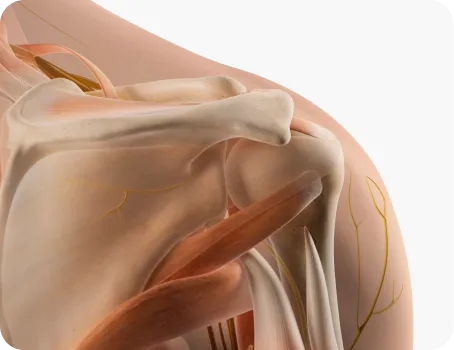

척추와 관절의 정상적인 정렬

당당 도수치료는 겉과 속을 같이 치료합니다.

뼈뿐만 아니라 근육의 불균형까지 함께 보고,

재발 방지를 위해 본인도 몰랐던 보행 패턴까지 바꿉니다.

질환별 맞춤 도수치료

통증 도수치료

한의사 + 의사 + 물리치료사의 협진을 통해

구조적·기능적 문제를 진단해

통증이 발생한 원인을 찾아 치료합니다.